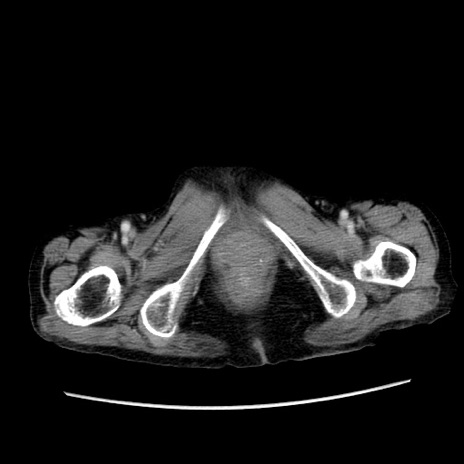

症例25(横断像)

症例

【症例】80歳代女性

【主訴】胸のつかえ感

【現病歴】約9時間前に食後から胸のつかえた感じあり、嘔吐あり、来院。

【既往歴】胃癌(全摘)、胆摘、虫垂炎

【身体所見】心窩部に圧痛あり、反跳痛なし。

【データ】WBC 5700、CRP 0.05